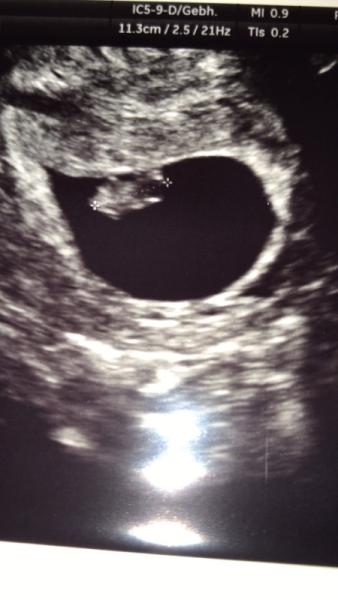

Hallo ihr Lieben! Heute hatte ich meinen ersten Ultraschall Das Kleine ist zeitgerecht entwickelt, das Herz schlägt und wir durften es hören. Bewegt hat es sich auch. Der nächste Termin ist ganz entspannt erst am 9.1. Die Gynäkologin sagte mir, dass alles so stimmig ist (also Dottersack, Embryo, Fruchthöhle) dass sie null bedenken hat, wegen des späten Termins. Ich bin einfach nur glücklich

Bild zu 1. Ultraschall - Forum für Juli - Mamis